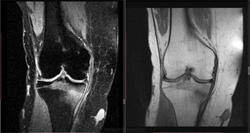

Женщина 1949 года рождения, жалуется на боли в правом коленном суставе в течении 2-х недель, травму категорически отрицает. Выполненна МРТ и рентгенография. Дайком. Какие версии?

Сам думаю о начальных проявлениях инфаркта костного мозга. Слева был перелом средней трети ББК.

1. Стресс перелом это одна вещь

2. Имеет четыре стадии, две с половиной из которых на рентгене не видно

3. В данном случае начало третей стадии

4. Нужно сделать рентген через месяц.

Формирующаяся линия перелома на сканах МРТ указана.

Благодарю за стрелочки! Смотрел, не поверил, отчего такой изломанный вид имеет линия перелома. А книга Ваша говорит, что это нормально для МРТ. Угу. Понял. Рентгенологически, значит, 3 стадии мы не видим.(